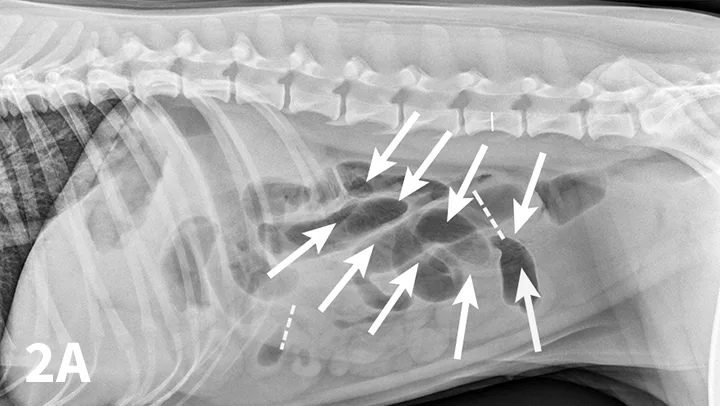

Right lateral (A) and VD (B) abdominal radiographs of a Labrador retriever with an obstructive ileus. A FB (sock) is present within a dilated small intestinal loop in the right caudoventral abdomen (arrows). The dashed lines outline a fluid-filled loop measuring 2.7 cm and a gas-filled loop measuring 2.4 cm, compared to the height of L5 (Asolid line, 1.1 cm);  the resulting ratios of 2.4 and 2.2, respectively, are much greater than the upper limit of 1.6 for normal small intestine to L5 height ratio. Several stacked gas-filled loops of small intestine are present in the left midabdomen (B).